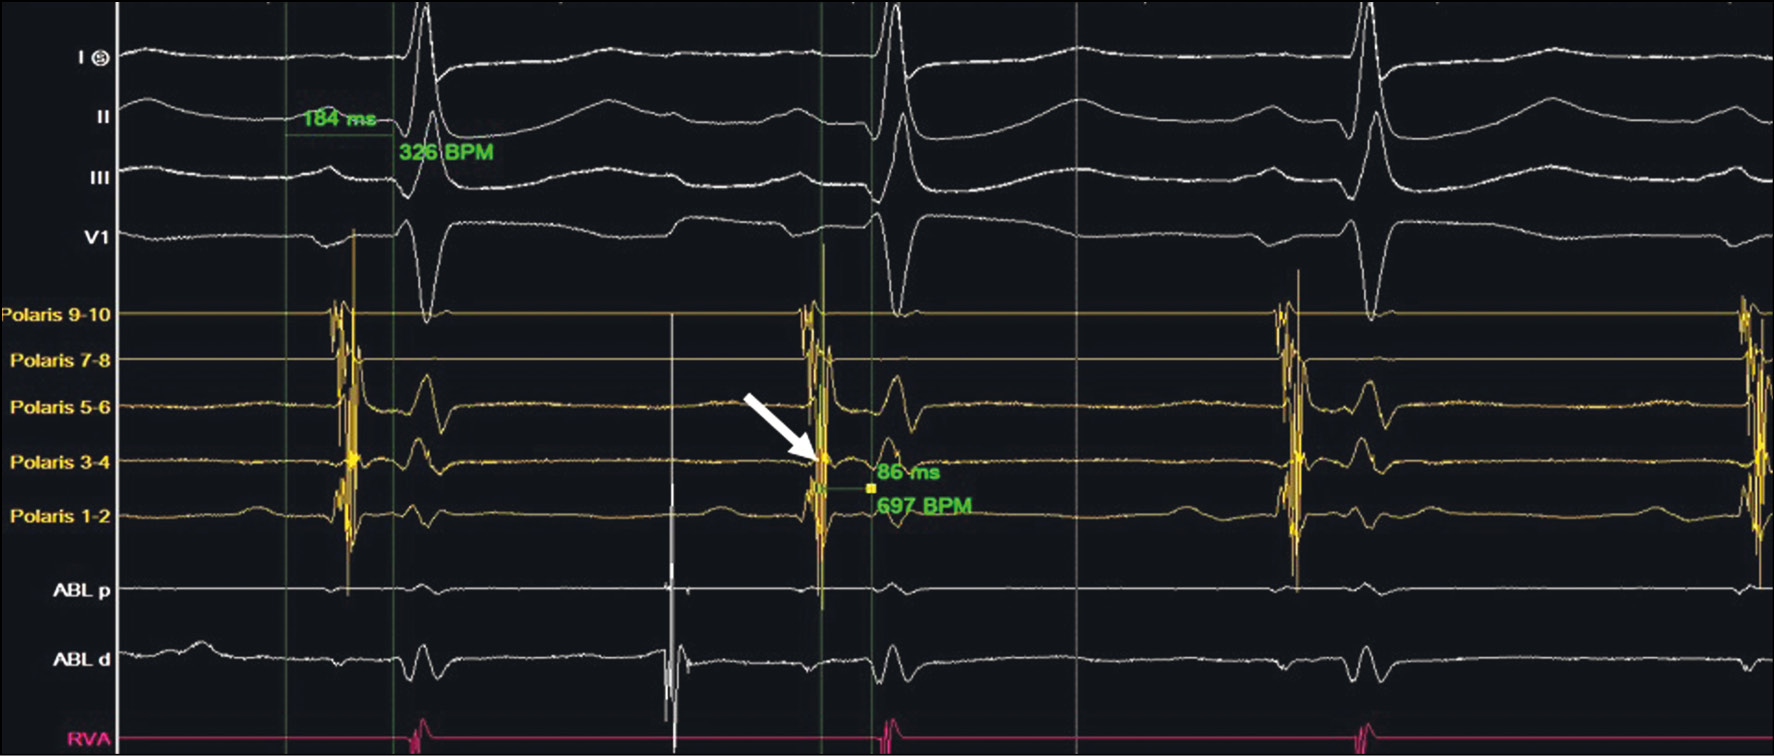

Для того чтобы отличить аберрацию проведения по левой ножке пучка Гиса (ЛНПГ) при наджелудочковой тахикардии от ортодромной АВРТ с ретроградным проведением по ДАВС с блокадой ЛНПГ, необходимо посчитать длину цикла тахикардии (расстояние между двумя соседними R-зубцами тахикардии, RR-интервал). На ЭКГ при тахикардии с «узкими» комплексами RR-интервал составляет 315 мс, при тахикардии с «широкими» комплексами — 400 мс (рис. 3).

Рис. 3. Длина цикла тахикардии изменяется с 400 до 315 мс. Разница в 85 мс соответствует увеличению длины петли риентри за счет того, что блокируется ЛНПГ, и электрический импульс распространяется к миокарду желудочков только по правой ножке пучка Гиса, возбуждая миокард правого желудочка, и только затем распространяется на миокард левого желудочка.

Fig. 3. The length of the tachycardia cycle changes from 400 msec to 315 msec. The 85 msec difference corresponds to the increase in the length of the re-entry loop, due to the left bundle branch block. The electric pulse propagates to the myocardium of the ventricles along the right bundle branch only, exciting the right ventricle myocardium, and only later propagates to the left ventricle myocardium.

При ортодромной АВРТ, сопровождающейся возникновением ипсилатерального блока проведения в системе левой ножки пучка Гиса, отмечается увеличение RR-интервала на 85 мс. Разница RR-интервалов заключается в том, что при блокировании ЛНПГ электрический импульс перенаправляется на миокард желудочков по правой ножке пучка Гиса, что и приводит к увеличению петли риентри и, соответственно, длины цикла тахикардии, в отличие от наджелудочковой тахикардии с блокадой ножки пучка Гиса, когда удлинения RR-интервала не происходит (RR-интервалы при «ширококомплексной» и «узкокомплексной» тахикардиях будут одинаковыми) [3–5].

Таким образом, на разбираемом фрагменте ХМ ЭКГ регистрируется удлинение цикла тахикардии с расширением комплексов QRS по типу блокады ЛНПГ, что говорит о наличии ортодромной АВРТ c участием левого ДАВС (ипсилатерально).